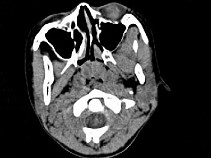

4.女,8歲,頭痛,鼻塞半年余,CT如圖所示,最可能診斷為  (    )

正確答案:C